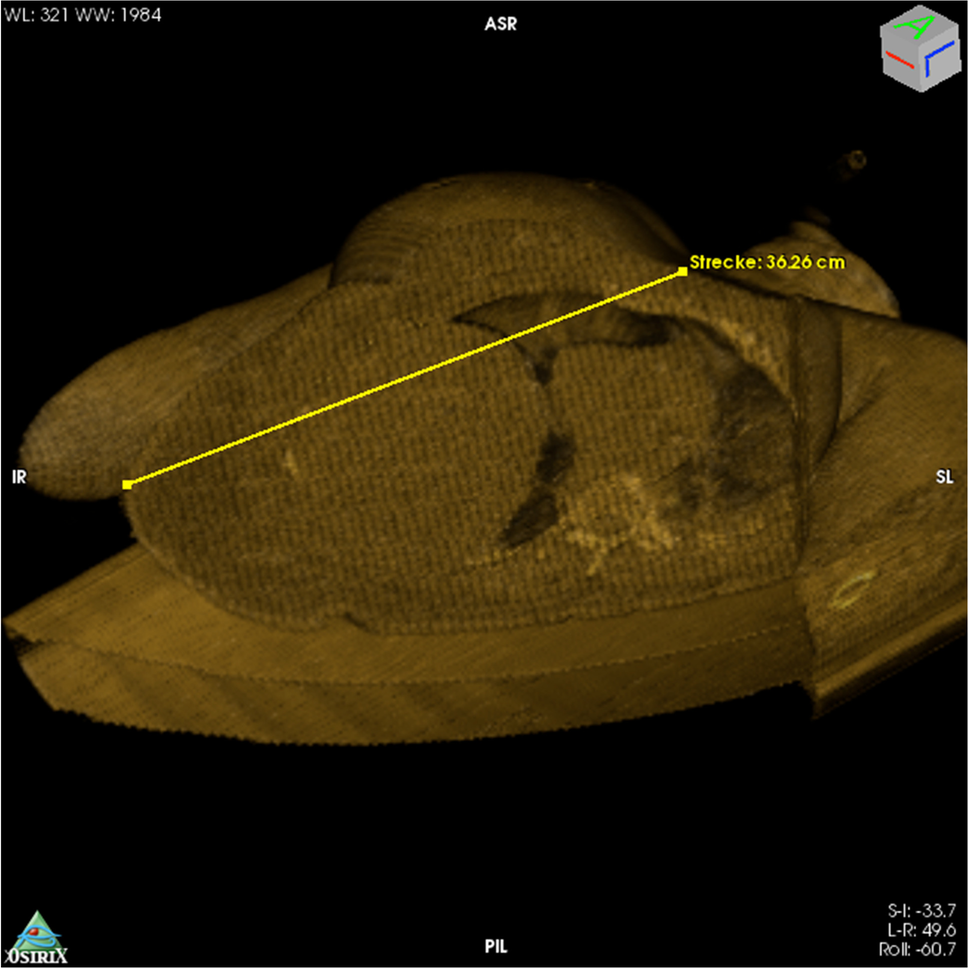

On the basis of the wound trajectory identified in 3D-reconstructed CT data, in which the bullet track was determined as a straight line from entry to exit wound (measured distance: 36 cm), the expectation had been that the bullet would have entered the thoracic and the abdominal cavities and that it would have perforated the right lung and the liver (Fig. 5).

Fig. 5

3D reconstructed CT datasets in volume-rendering mode, depicting the virtual wound trajectory and measurement of the straight connection between entry and exit wounds. After aligning the torso in the frontal plane, the cutting tool in OsiriX was used to cut the image along the bullet track. The parts of the torso that faced towards the lower left were eliminated. The ensuing cross section was then aligned in the frontal plane, and the exit and entry wounds were connected, using a measuring tool. The approximately 36-cm-long bullet trajectory can be seen to pass through the thoracic and the abdominal cavities

The wound track left by the third, tangential, bullet was, however, so unusual that we believe it merits reporting. In the trajectory analysis of this wound from 3D reconstructed CT data sets, the linear distance measured between entry and exit wounds was approximately 36 cm. In this straight trajectory through the body, the bullet would have had to traverse the thoracic and abdominal cavities; however, the actual wound channel was not found to pass through either of these cavities. The bullet had, instead, followed an approximately 40-cm-long, nonlinear trajectory though the subcutaneous adipose tissue. Contact with bone could be excluded as a reason for bullet deflection. The contusion in the medial lobe of the right lung and the hemorrhage in the adipose tissue around the right kidney were, therefore, likely caused by expansion of the temporary cavity around the wound channel.